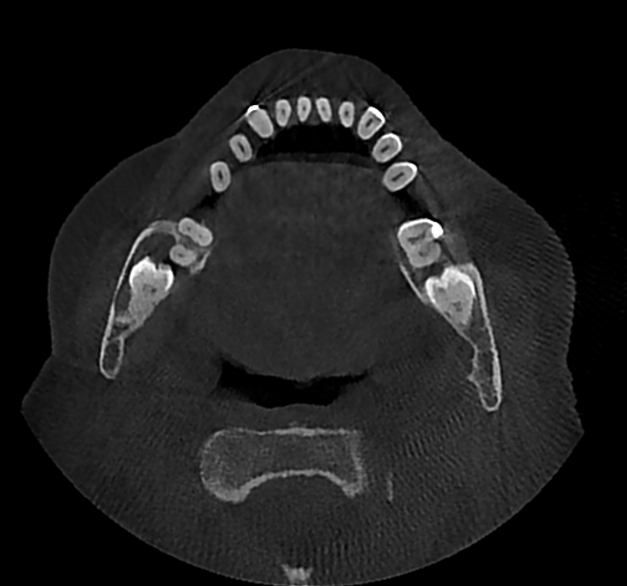

Pacjentka przyjmowała na stałe rywaroksaban i kwas acetylosalicylowy z powodu zakrzepicy żył głębokich kończyn dolnych oraz leki na nadciśnienie tętnicze – walsartan i amlodypinę. W badaniu zewnątrzustnym nie stwierdzono odchyleń od normy. W badaniu wewnątrzustnym stwierdzono chełbotanie wyczuwalne od strony przedsionkowej i językowej po stronie prawej żuchwy. W badaniu CBCT stwierdzono zmianę o charakterze osteolitycznym wielkości 43 mm × 41 mm × 12 mm (w największym wymiarze), która zajmowała prawy trzon, kąt i gałąź żuchwy oraz obejmowała drugi (ząb 47) oraz trzeci ząb trzonowy (ząb 48). Zmiana perforowała blaszkę zbitą od strony przedsionkowej i językowej (ryc. 1). Zaplanowano zabieg w znieczuleniu miejscowym. Dobę przed zabiegiem u pacjentki wdrożono antybiotykoterapię w postaci klindamycyny (300 mg), stosowanej co 8 godzin.

Ryc. 1. Badanie CBCT: a) rekonstrukcja pantomograficzna; b) przekrój poprzeczny; c) przekrój strzałkowy – widoczna zmiana o charakterze osteolizy, związana z zatrzymanym zębem 48 (listopad 2020).